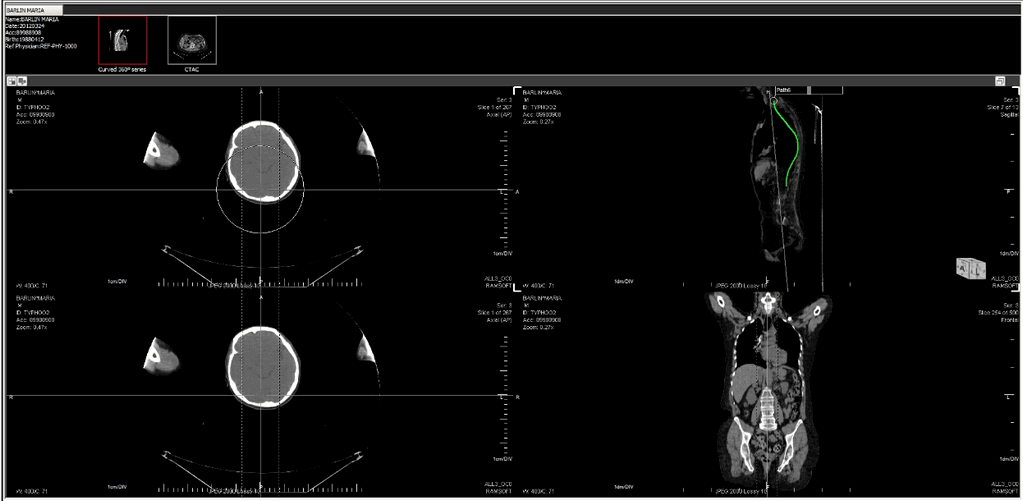

Creating a 360 degree series centered on the path

Choosing the Create new 360 degree series centered on path will extract the area selected and create a Curved 360 degree MPR . Choosing this option will open up a sub-menu.

The user must choose the number of slices/steps and the increment in degrees for the angles of the slice. Clicking OK creates a series and places it above the viewport. As in the above example, the new series at the top contains ten images or slices.